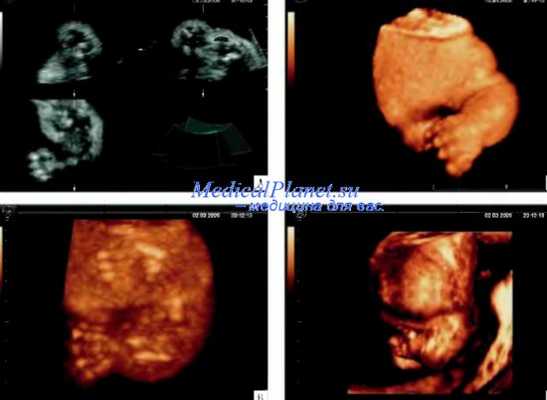

Рис. 20.3. Танатофорная дисплазия. А и Б - поверхностная реконструкция. Видны укороченные конечности и узкая грудная клетка. В - фенотип абортуса.

Рис. 20.4. Танатофорная дисплазия. А, Б - поверхностная реконструкция структур лица. В - фенотип абортуса [6].